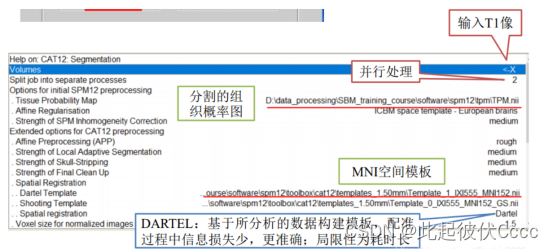

(3)点击segment,进入如下界面:

选择需要处理的T1图像,参数配置好后点击左上角的小三角运行即可:

点击后出现如下运行界面: